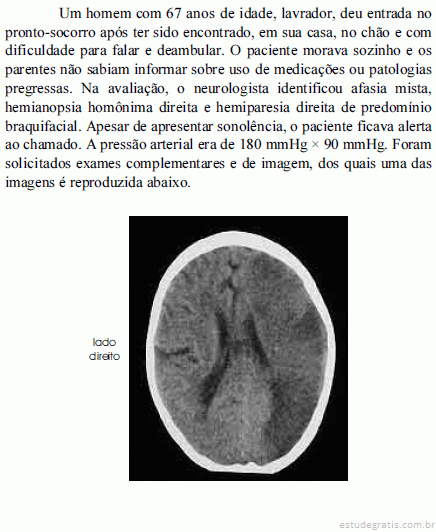

A hemorragia subaracnóide é causa de cefaléia e convulsões. Uma complicação desse tipo de sangramento é o vasoespasmo, que pode causar acidente vascular cerebral isquêmico e resultar em quadro clínico semelhante ao ilustrado.